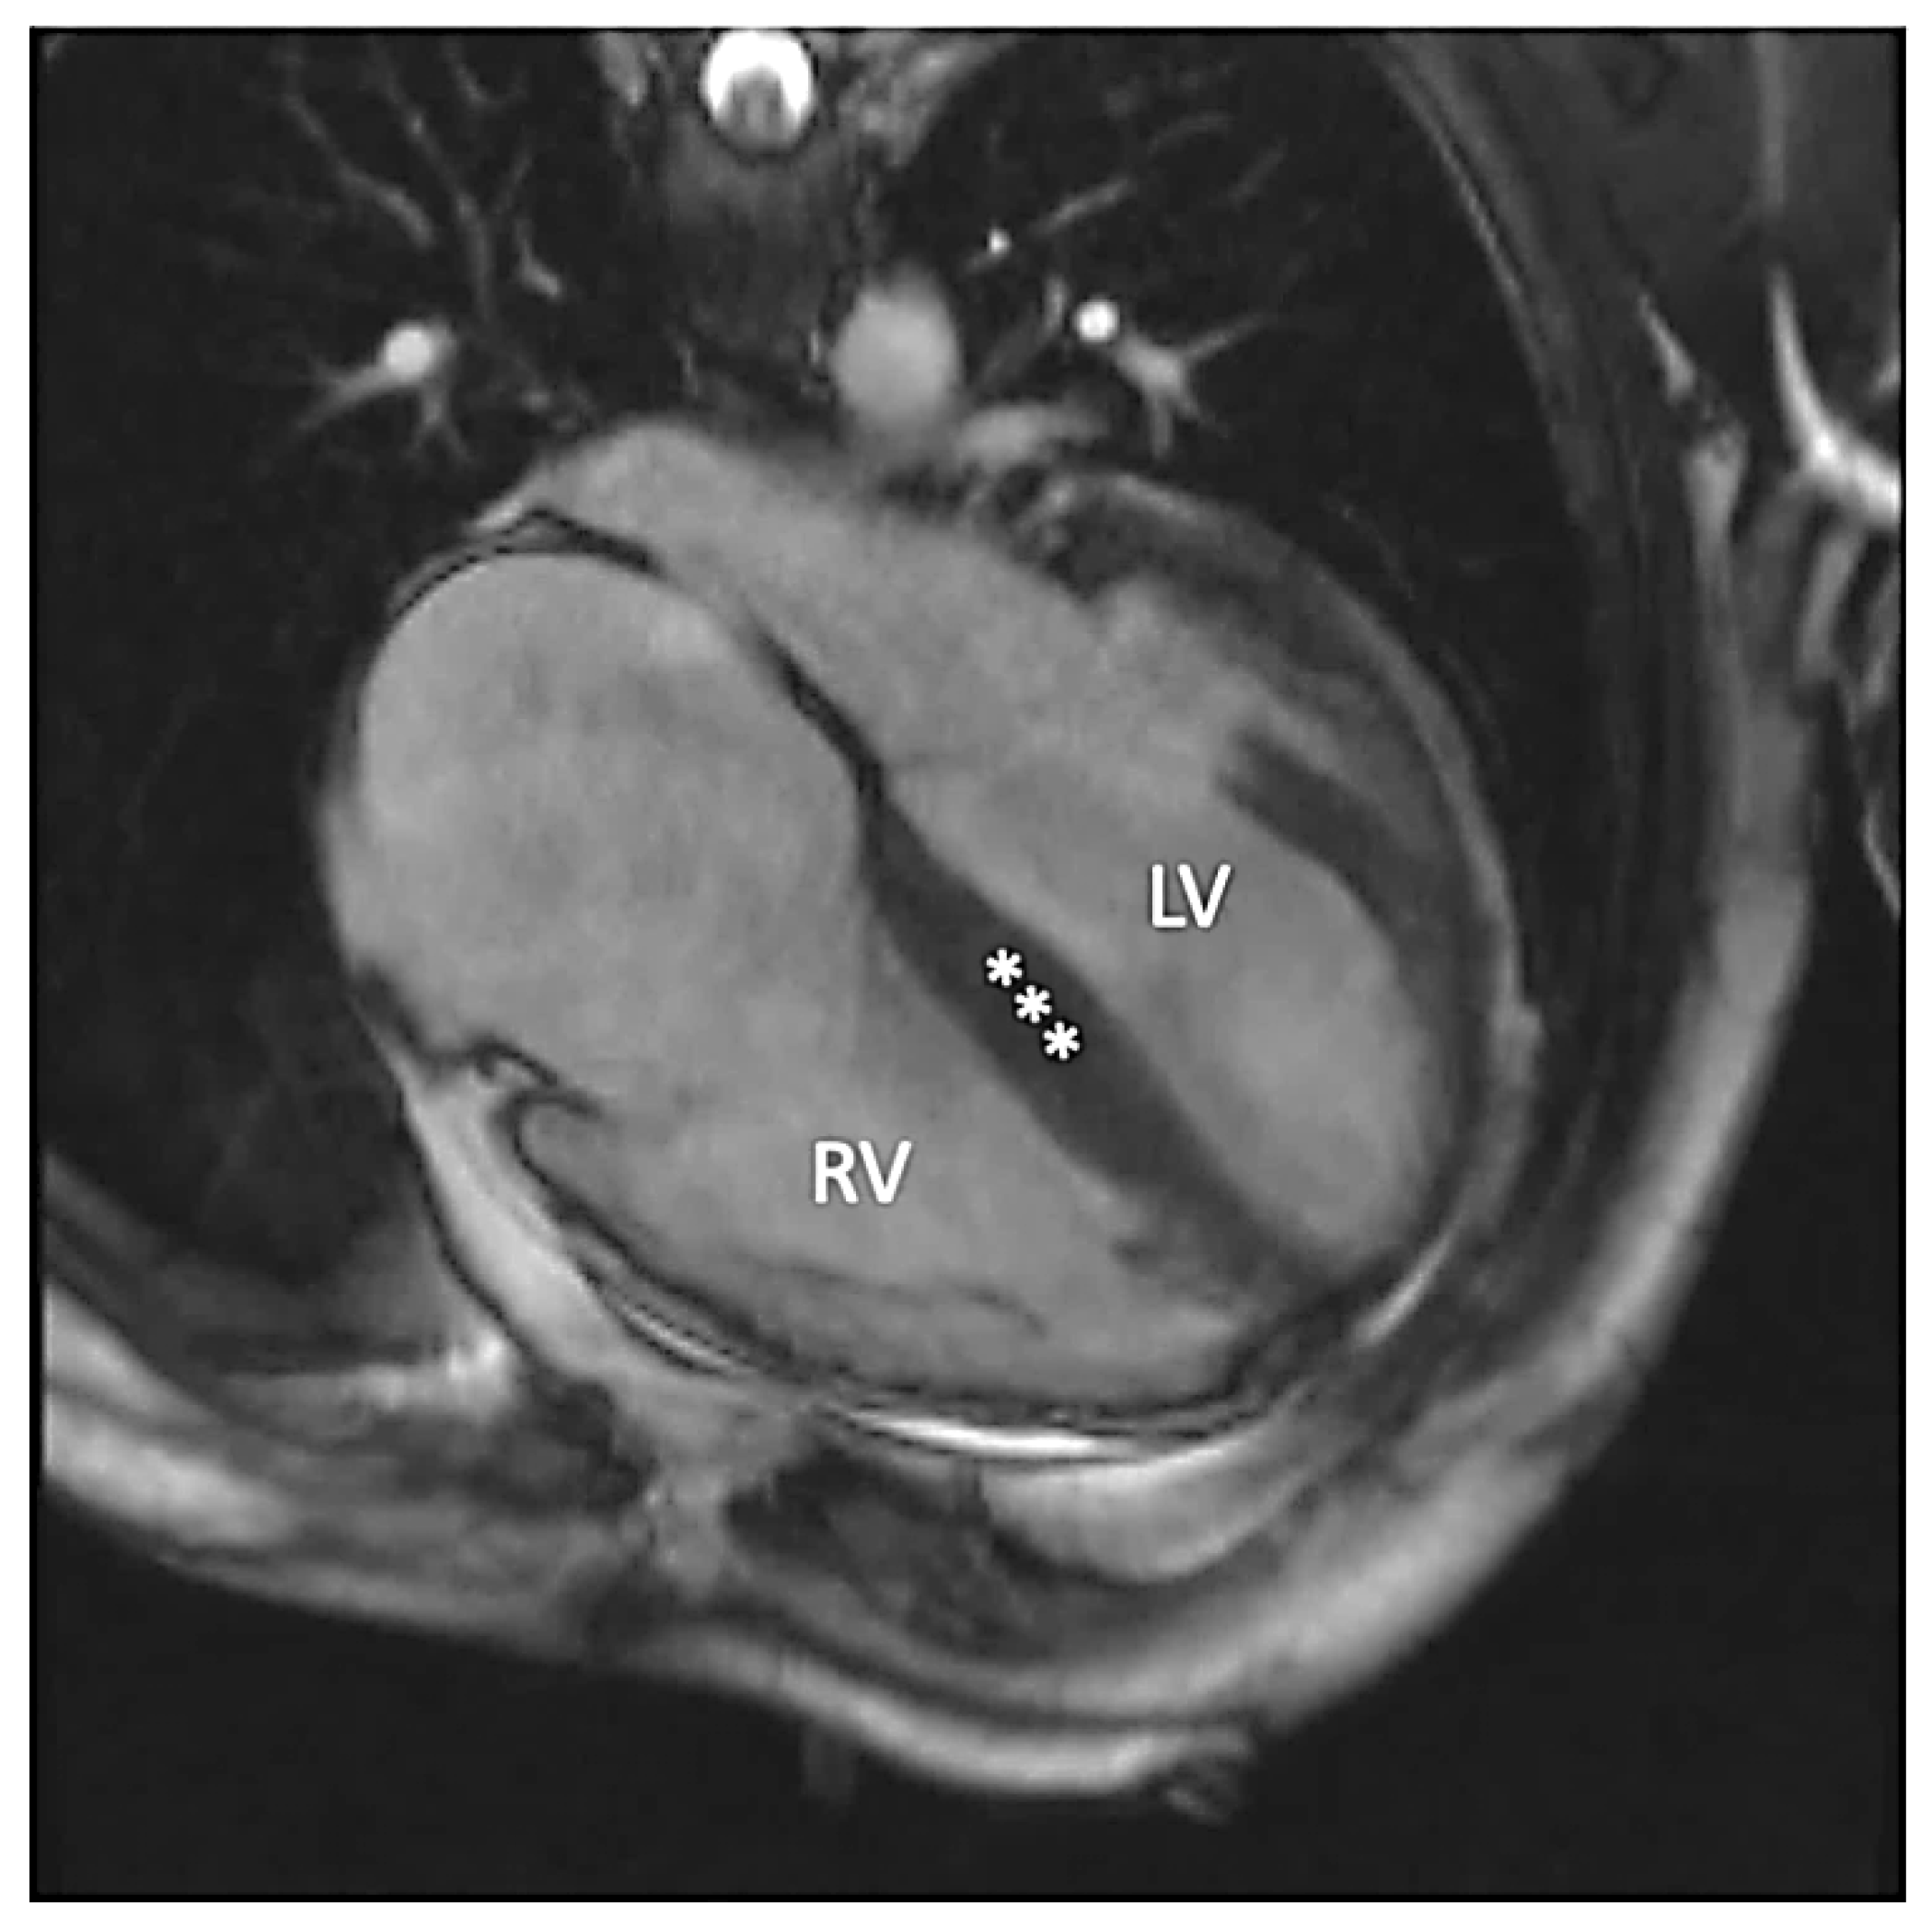

Figure 4.

Late gadolinium enhancement four-chamber image demonstrating diffuse fibrosis in the left (LV) and the right ventricles (RV).